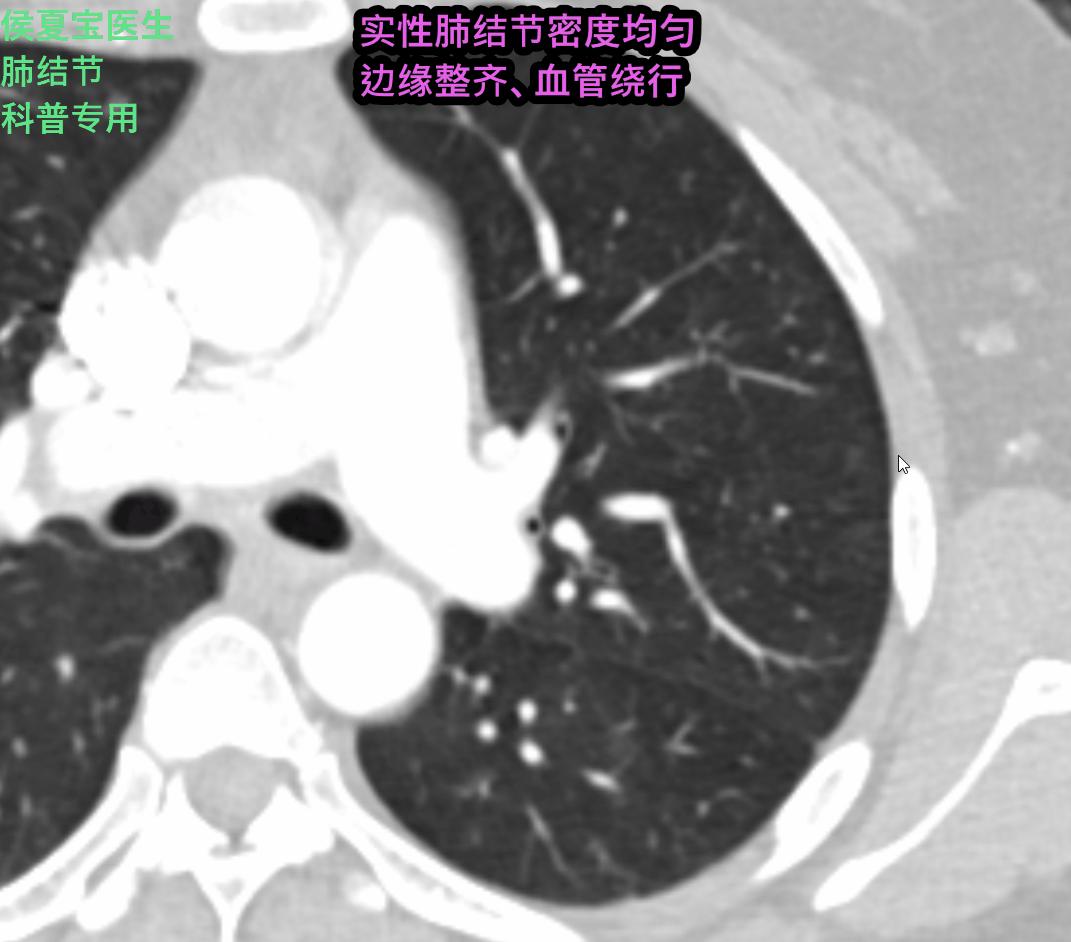

但看到同行朋友发过来的截图视频,虽不是高清,我总觉得那种典型的“血管结节外旁开”的影像,也许不是典型的恶性影像呢?于是我电话告知:复查薄层增强CT,上传光盘数据。侯医生要依己之力来严肃回答“是什么”的问题。

进一步进行VR的微血管重建,更能清晰的看到几乎一目了然的“血管旁开”,也就是血管均走行于肺结节的外部,相比于恶性肿瘤分泌“血管生成因子”促使新生血管的进入、紊乱、异常交通有很大的区别。

对于肺实性结节的影像诊断,侯医生始终不敢涉及,毕竟“良性很良、恶性更恶”在临床工作中、专业交流、个案报道中、媒体渲染中吸尽“眼球”,虽然“毛刺、气管截断、胸膜牵拉、增强强化”等等特征在实体瘤的经典表现人尽皆知,但对于肺小实性结节(1cm左右)首次发现后,对于那些典型良性影像表现的,侯医生均建议“治疗后20天左右复查对比”。

综合更多细节的甄别和量化分析,这一枚结节,我最终回复给同行朋友个人的影像诊断意见:良性肺血管性肿瘤,硬化性肺细胞瘤(硬化性血管瘤)首先考虑,恶性几率极小。